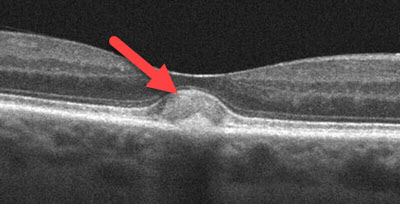

Most macular dystrophies are detected during a dilated ocular examination. A central yellow spot or a variable pattern of yellow spots is seen in each macula. OCT scanning and fluorescein angiography are often used to confirm the diagnosis. Patients are often misdiagnosed as having age-related macular degeneration since the findings can appear somewhat similar.